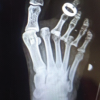

At 2 weeks follow-up, there was no evidence of hardware migration, the thumb was well-reduced, and the patient was placed in a thumb spica cast (Fig. 2). The pin and cast were removed at 7 weeks (Fig. 3), at which time the patient exhibited signs of good clinical healing and was provided a thumb spica brace.

At 1-year follow-up, the patient reported good function of the thumb with no instances of IP joint dislocation. Passive hyperextension of the IP joint was noted on physical exam, but she could not be dislocated passively. In addition, the IP joint remained reduced with flexion and extension (Fig. 4), and she could pinch without IP joint subluxation or dislocation (Fig. 5). The patient was pain-free in her thumb. Final radiographic imaging at this time demonstrated stable fixation of the thumb without evidence of hardware migration or failure (Fig. 6).